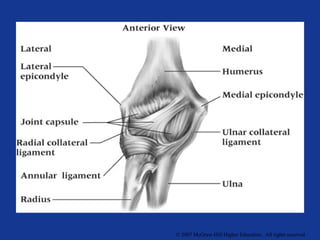

Medial Collateral Ligament (MCL)

Anterior

Medial

Collateral

Ligament

Posterior

Resists valgus

forces

Limits extension

Transverse ligament

Lateral Collateral

Resists varus stress

Weaker than MCL

Tensed in flexion and

extention